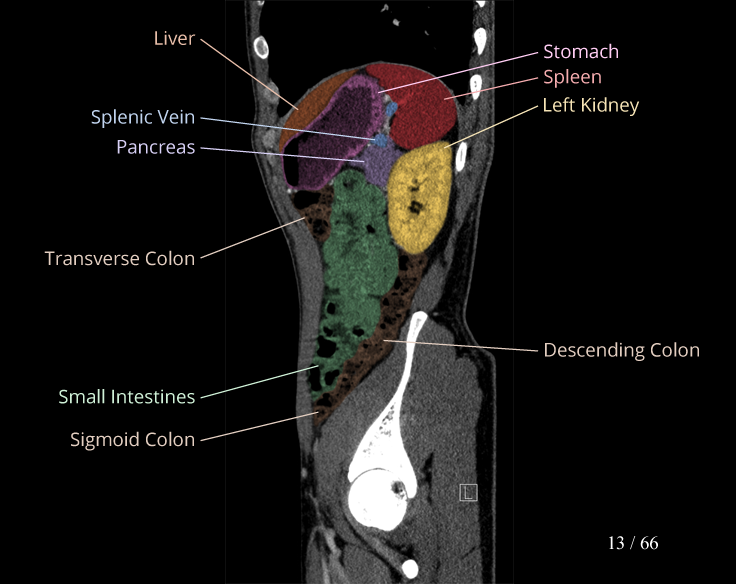

Body

Covers abdominal CT anatomy.